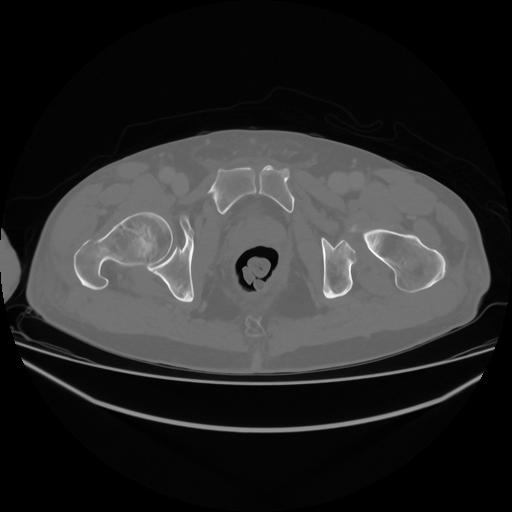

5 CUERPO,CE,Vol,1.0,CUERPO,,